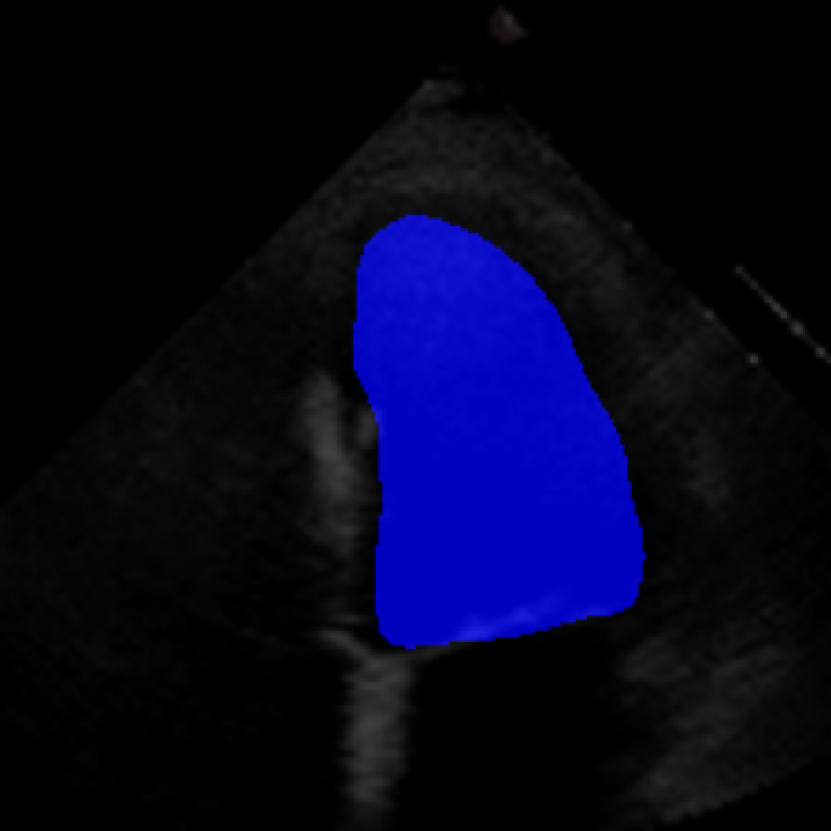

The 112x112 input is first resized to 299x299 as required by the Xception model. The Beat Extractor is then used to feed only whole beats to the LVEF estimation pipeline. A modified DeepLabV3+ model segments the left ventricle for every frame of the echocardiogram video (Figure LABEL:fig:segmentation). The area is measured, and a peak detector is then used to find the maximum (diastole) and minimum area (systole). The frame numbers corresponding to these extrema are recorded, and the video is clipped into smaller videos that go from diastole to systole. These smaller videos are independently fed to the Xception based feature extractor.

The ConFormer model demonstrated high performance in the estimation of Left Ventricular Ejection Fraction (LVEF) from echocardiogram videos (Figure 2). The model achieved a mean absolute error of 6.57 in LVEF prediction, indicating a high level of accuracy in its estimations (Table I). Notably, ConFormer outperforms the full video assessment of LVEF by EchoNet-Dynamic, a significant achievement given the model’s efficiency. With just 5.82 million parameters, ConFormer is significantly more efficient than existing models, making it a practical tool for real-world applications.